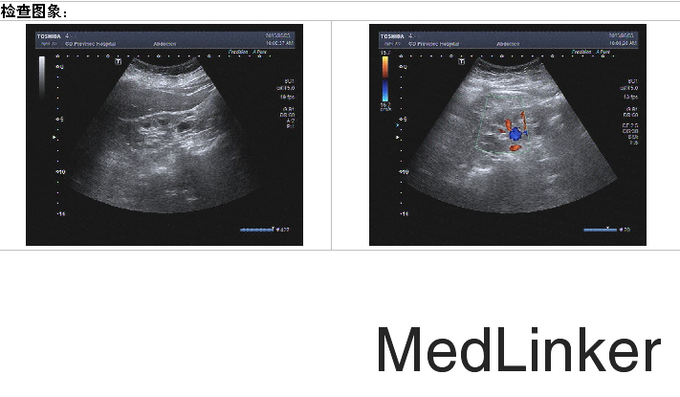

颜面及眼睑无水肿,心肺腹查体未见明显异常,输尿管点无压痛,双侧肾区无叩痛,移动性浊音阴性,四肢无水肿。、 24h尿白蛋白总量 30mg;24h尿液蛋白定量 75mg; 生化:尿素氮 8.63mmol/L ↑;肌酐 283umol/L ↑;钙 2.28mmol/L ;钾 4.48mmol/L ;尿酸 550.0 umol/L,肌酐 268.00 umol/L,甘油三酯 2.37 mmol/L。 复查生化急诊八项:尿素氮 6.86mmol/L ;肌酐 214umol/L ↑;钙 2.44mmol/L ;钠 122mmol/L ↓;钾 4.16mmol/L ; 最后一次复查生化急诊八项:尿素氮 8.49mmol/L ↑;肌酐 190.12umol/L ↑;钙 2.52mmol/L ;钠 138.4mmol/L 。 血常规正常。 腹部B超:1.双肾缩小、回声异常(考虑慢性肾脏疾病声像图改变,请结合临床);双肾囊肿。